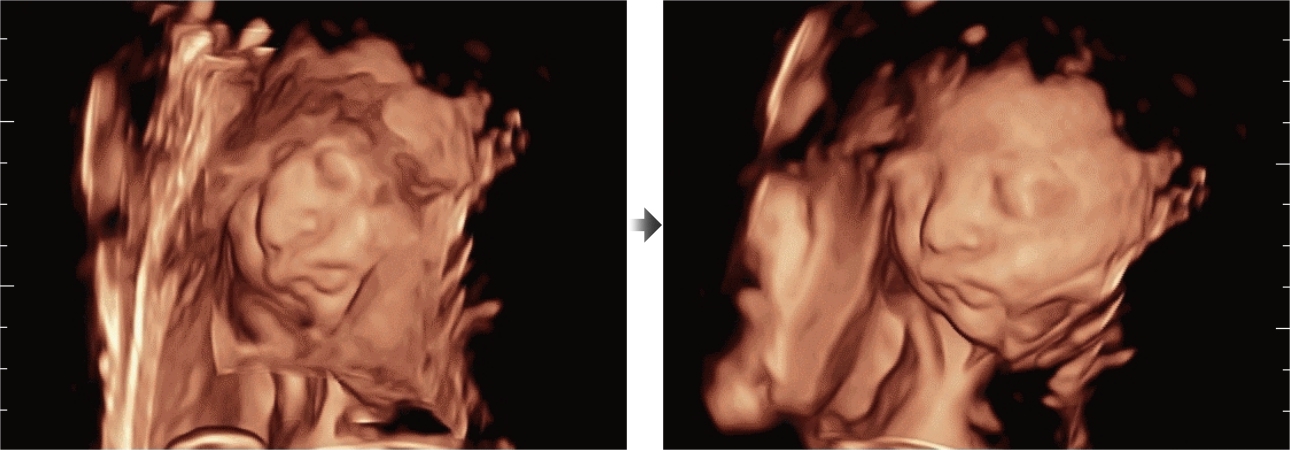

Selain kualitas gambar premium, Resona 7 juga meningkatkan kemampuan penelitian klinis dengan V Flow revolusioner untuk evaluasi hemodinamika vaskular, serta pengambilan penampang tercanggih dari rangkaian data 3D untuk diagnosis CNS pada janin. Kombinasi pengoperasian multisentuh berbasis gerakan yang paling intuitif dengan semua fitur klinis penting membuat Resona 7 menjadi gebrakan baru dalam inovasi ultrasound.